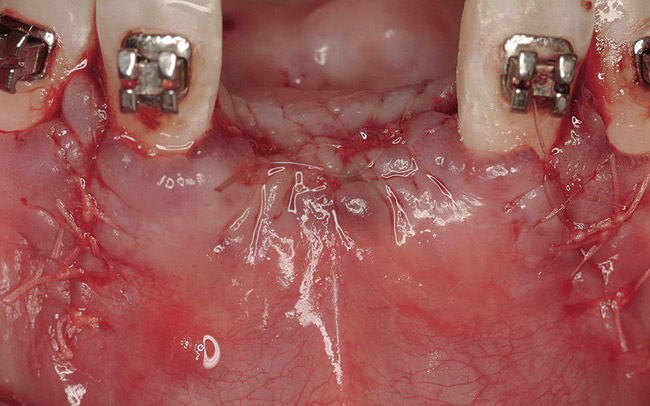

Figure 16  The edentulous anterior sextant. Portions of the facial bony wall remain in the maxillary left central and lateral incisor region. The long-standing abscess associated with tooth Nos. 7 and 8 has resulted in total loss of the bony plate in this area.

Figure 16